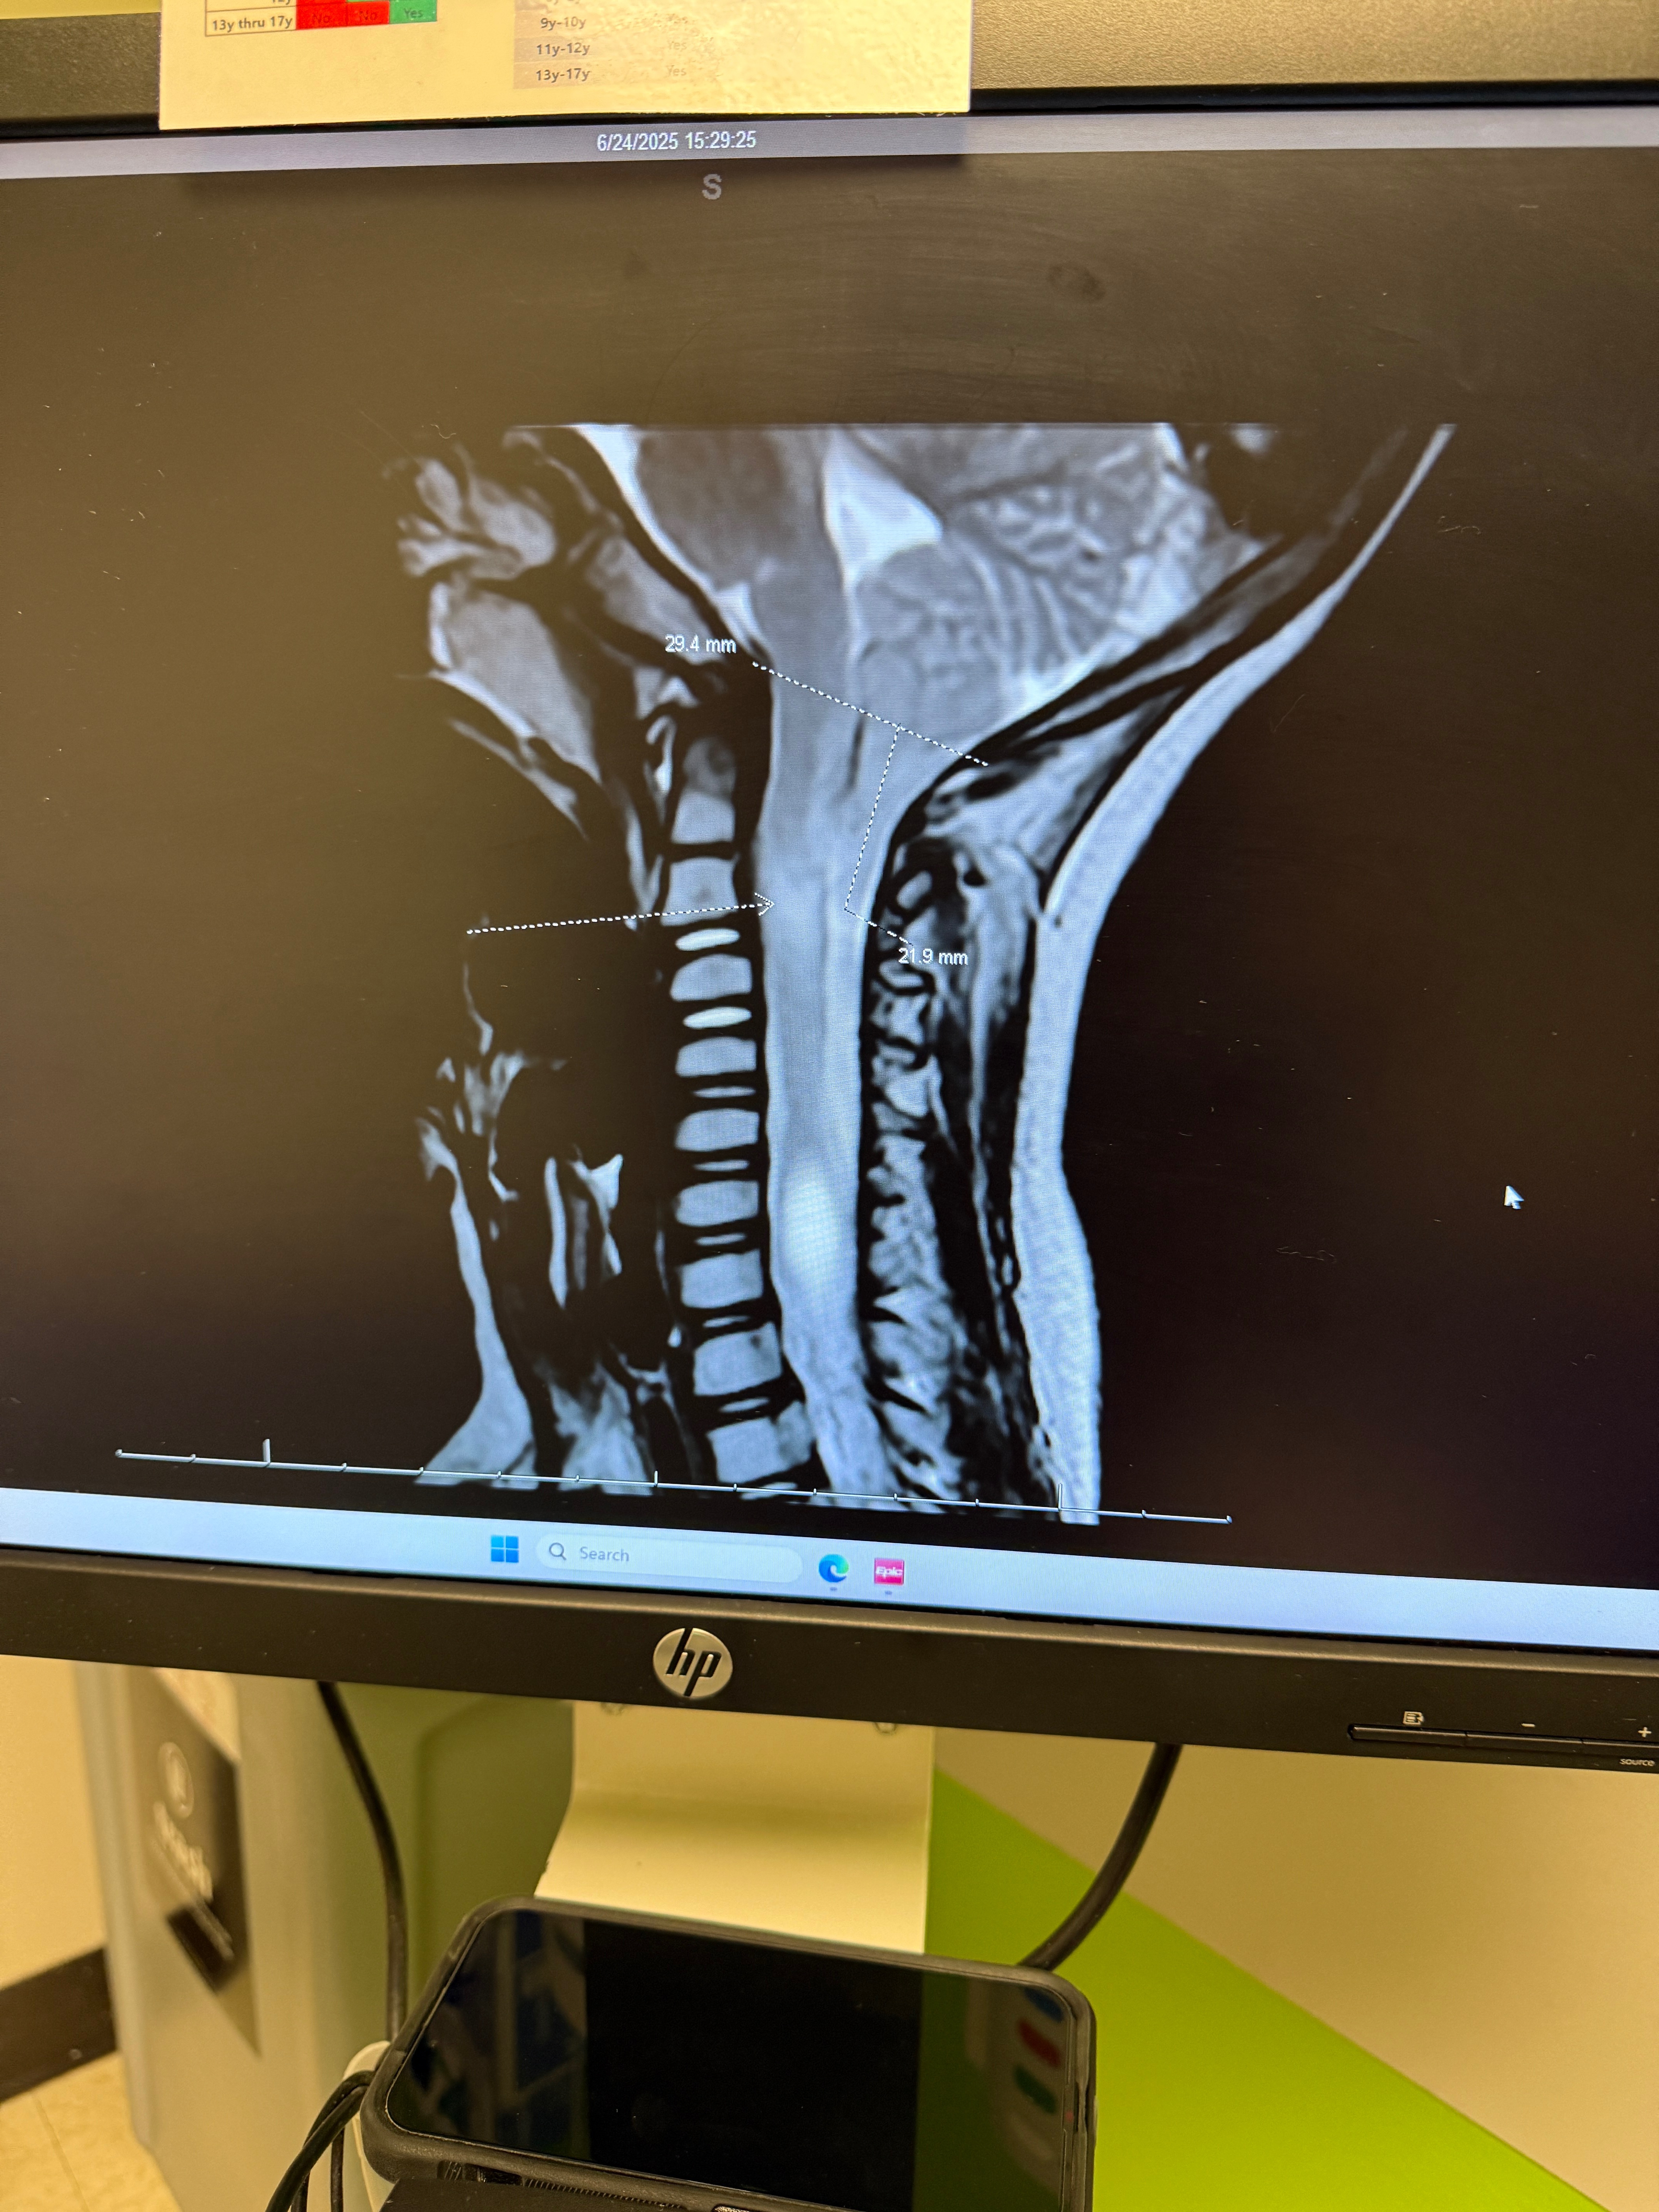

On June 24th Edgar had a MRI ordered by his eye doctor from having continuous eye pain over the last six months. What they found on the MRI was not what we were expecting at all. He was diagnosed with Arnold Chiari Malformation Type 1. We were told he had an over abundance of brain fluid, creating swelling in his brain and that we needed to follow up with a Neurosurgeon in LA.

The doctor explained how Edgar’s brain has slipped 22 mm down his spinal canal to his second vertebrae in his neck. He’s on heavy restriction till the surgery. He’ll be in ICU after surgery for a few days recovering. Once at home, he’ll be on bedrest for two weeks. He’ll sleep upright or slightly elevated for 6 weeks. He won’t be allowed to be submerged in water for 6 weeks as well. He has follow up appointments set after surgery on August 5th and September 9th both in LA.